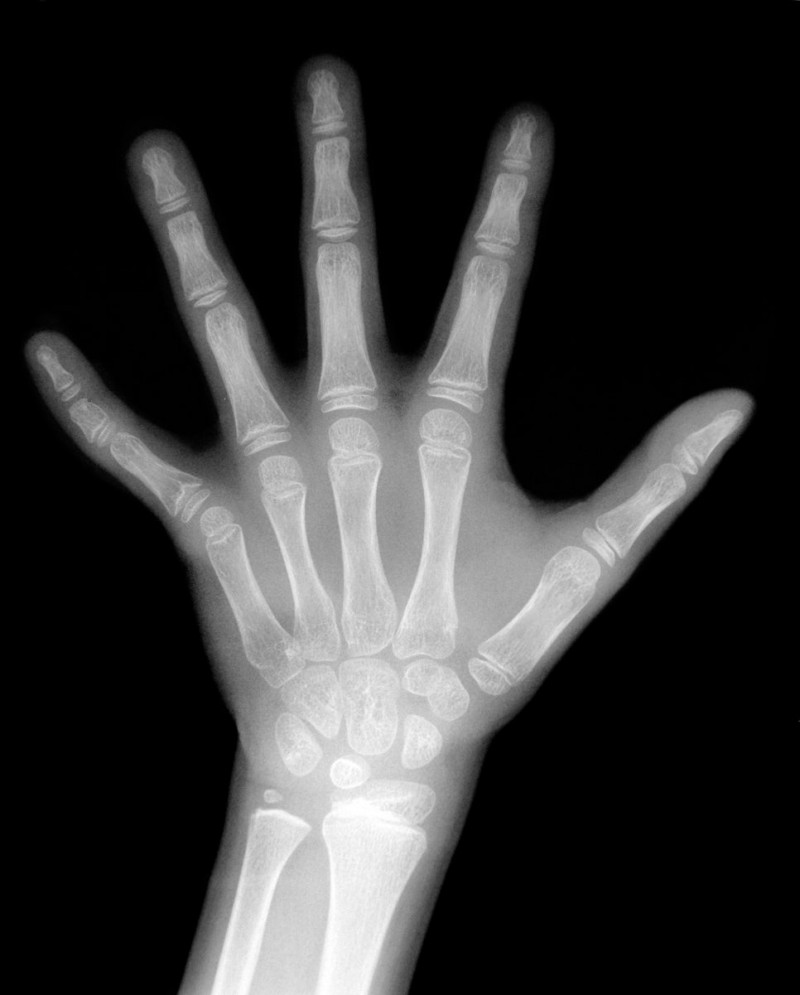

✔ 가장 기본적인 방법은 X-ray 촬영입니다.

보통 왼손과 손목 부위를 찍는데, 이 부위가 뼈의 성장 상태를 가장 명확하게 보여주기 때문이에요.

촬영 시간은 5분도 채 걸리지 않아서 아이도 부담 없이 받을 수 있어요.

✔ 골연령(뼈 나이) 분석

촬영한 사진을 표준 뼈 나이 자료와 비교해 아이의 '뼈 나이'를 산출합니다.

예를 들어 아이의 실제 나이는 11세인데 뼈 나이가 9세라면, 또래보다 더 클 여지가 많다는 의미예요.

반대로 뼈 나이가 실제보다 많다면 성장이 빠르게 끝날 수도 있겠죠.